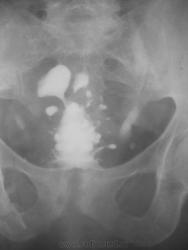

В подтверждение наличия хр.симфизитов при хр.заболеваниях урогенитальной зоны - женщина, хр.цистит, специфические изменения лонного сочленения....

hr_simfizit1.jpg

Интересный случай.